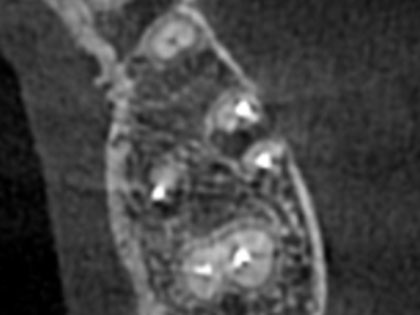

• 歯根端切除の術前1

• 歯根端切除の術前2

• 歯根端切除の術前3

• 歯根端切除の術前4

• 歯根端切除の術前5